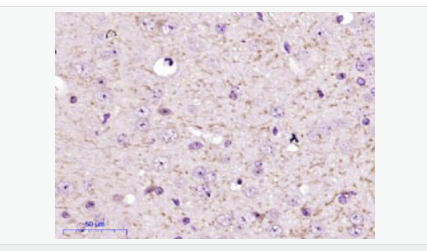

image.png